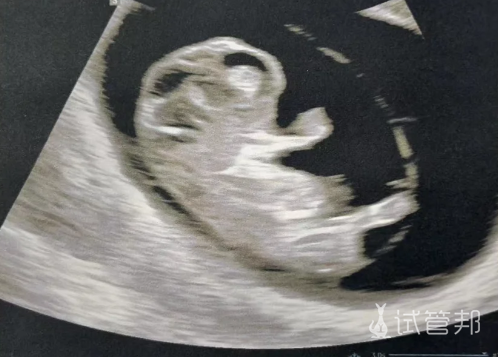

我的宝贝终于迎来了他/她的首张“萌照”,从春意盎然的2月20日踏上助孕之旅,历经半年多的时光洗礼,直至8月11日,我们圆满结束了在生殖科的这段特殊旅程,共计174个日夜的坚持与期盼,迎来圆满结局。

手捧这份珍贵的“毕业照”,我和伴侣的眼眶都不禁湿润了,那是对即将降临的小生命无限的爱与期待,也是对自己勇敢与坚持的深深感慨。感谢宝贝的选择与配合,让我们的家庭即将迎来新的成员;感谢伴侣的陪伴与支持,成为我最坚实的后盾。更感激上天的眷顾与巧妙安排,让这一切成为可能。